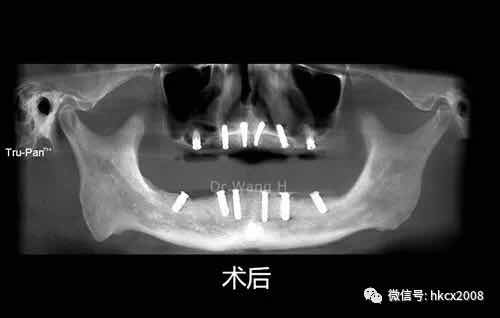

说这番话的是,来自福建的张老师,在杭州口腔医院城西院区特需专家科王辉主任团队402诊室顺利完成全口种植牙修复。